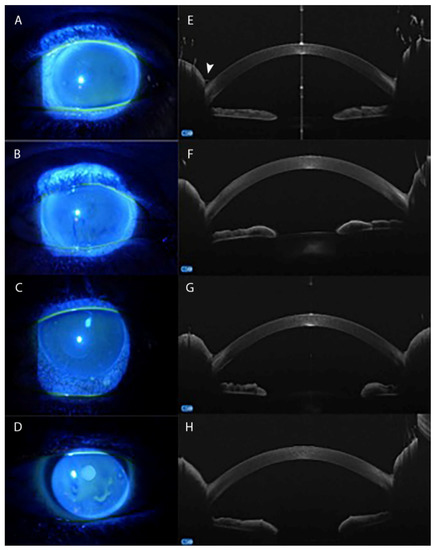

| Fea A. et al. [97] | 2017 | IVCM a AS-OCT j | POAG e | XEN 45 gel stent implant | |

- Fea, A.M.; Spinetta, R.; Cannizzo, P.M.L.; Consolandi, G.; Lavia, C.; Aragno, V.; Germinetti, F.; Rolle, T. Evaluation of Bleb Morphology and Reduction in IOP and Glaucoma Medication following Implantation of a Novel Gel Stent. J. Ophthalmol. 2017, 2017, 9364910. [Google Scholar] [CrossRef] [PubMed]

- Olate-Pérez, A.; Pérez-Torregrosa, V.T.; Gargallo-Benedicto, A.; Neira-Ibáñez, P.; Cerdà-Ibáñez, M.; Osorio-Alayo, V.; Barreiro-Rego, A.; Duch-Samper, A. Prospective study of filtering blebs after XEN45 surgery. Arch. Soc. Esp. Oftalmol. 2017, 92, 366–371. [Google Scholar] [CrossRef] [PubMed]

- Lenzhofer, M.; Strohmaier, C.; Hohensinn, M.; Hitzl, W.; Sperl, P.; Gerner, M.; Steiner, V.; Moussa, S.; Krall, E.; Reitsamer, H.A. Longitudinal bleb morphology in anterior segment OCT after minimally invasive transscleral ab interno Glaucoma Gel Microstent implantation. Acta Ophthalmol. 2019, 97, e231–e237. [Google Scholar] [CrossRef]

- Teus, M.A.; Moreno-Arrones, J.P.; Castaño, B.; Castejon, M.A.; Bolivar, G. Optical coherence tomography analysis of filtering blebs after long-term, functioning trabeculectomy and XEN® stent implant. Graefes Arch. Clin. Exp. Ophthalmol. 2019, 257, 1005–1011. [Google Scholar] [CrossRef] [PubMed]